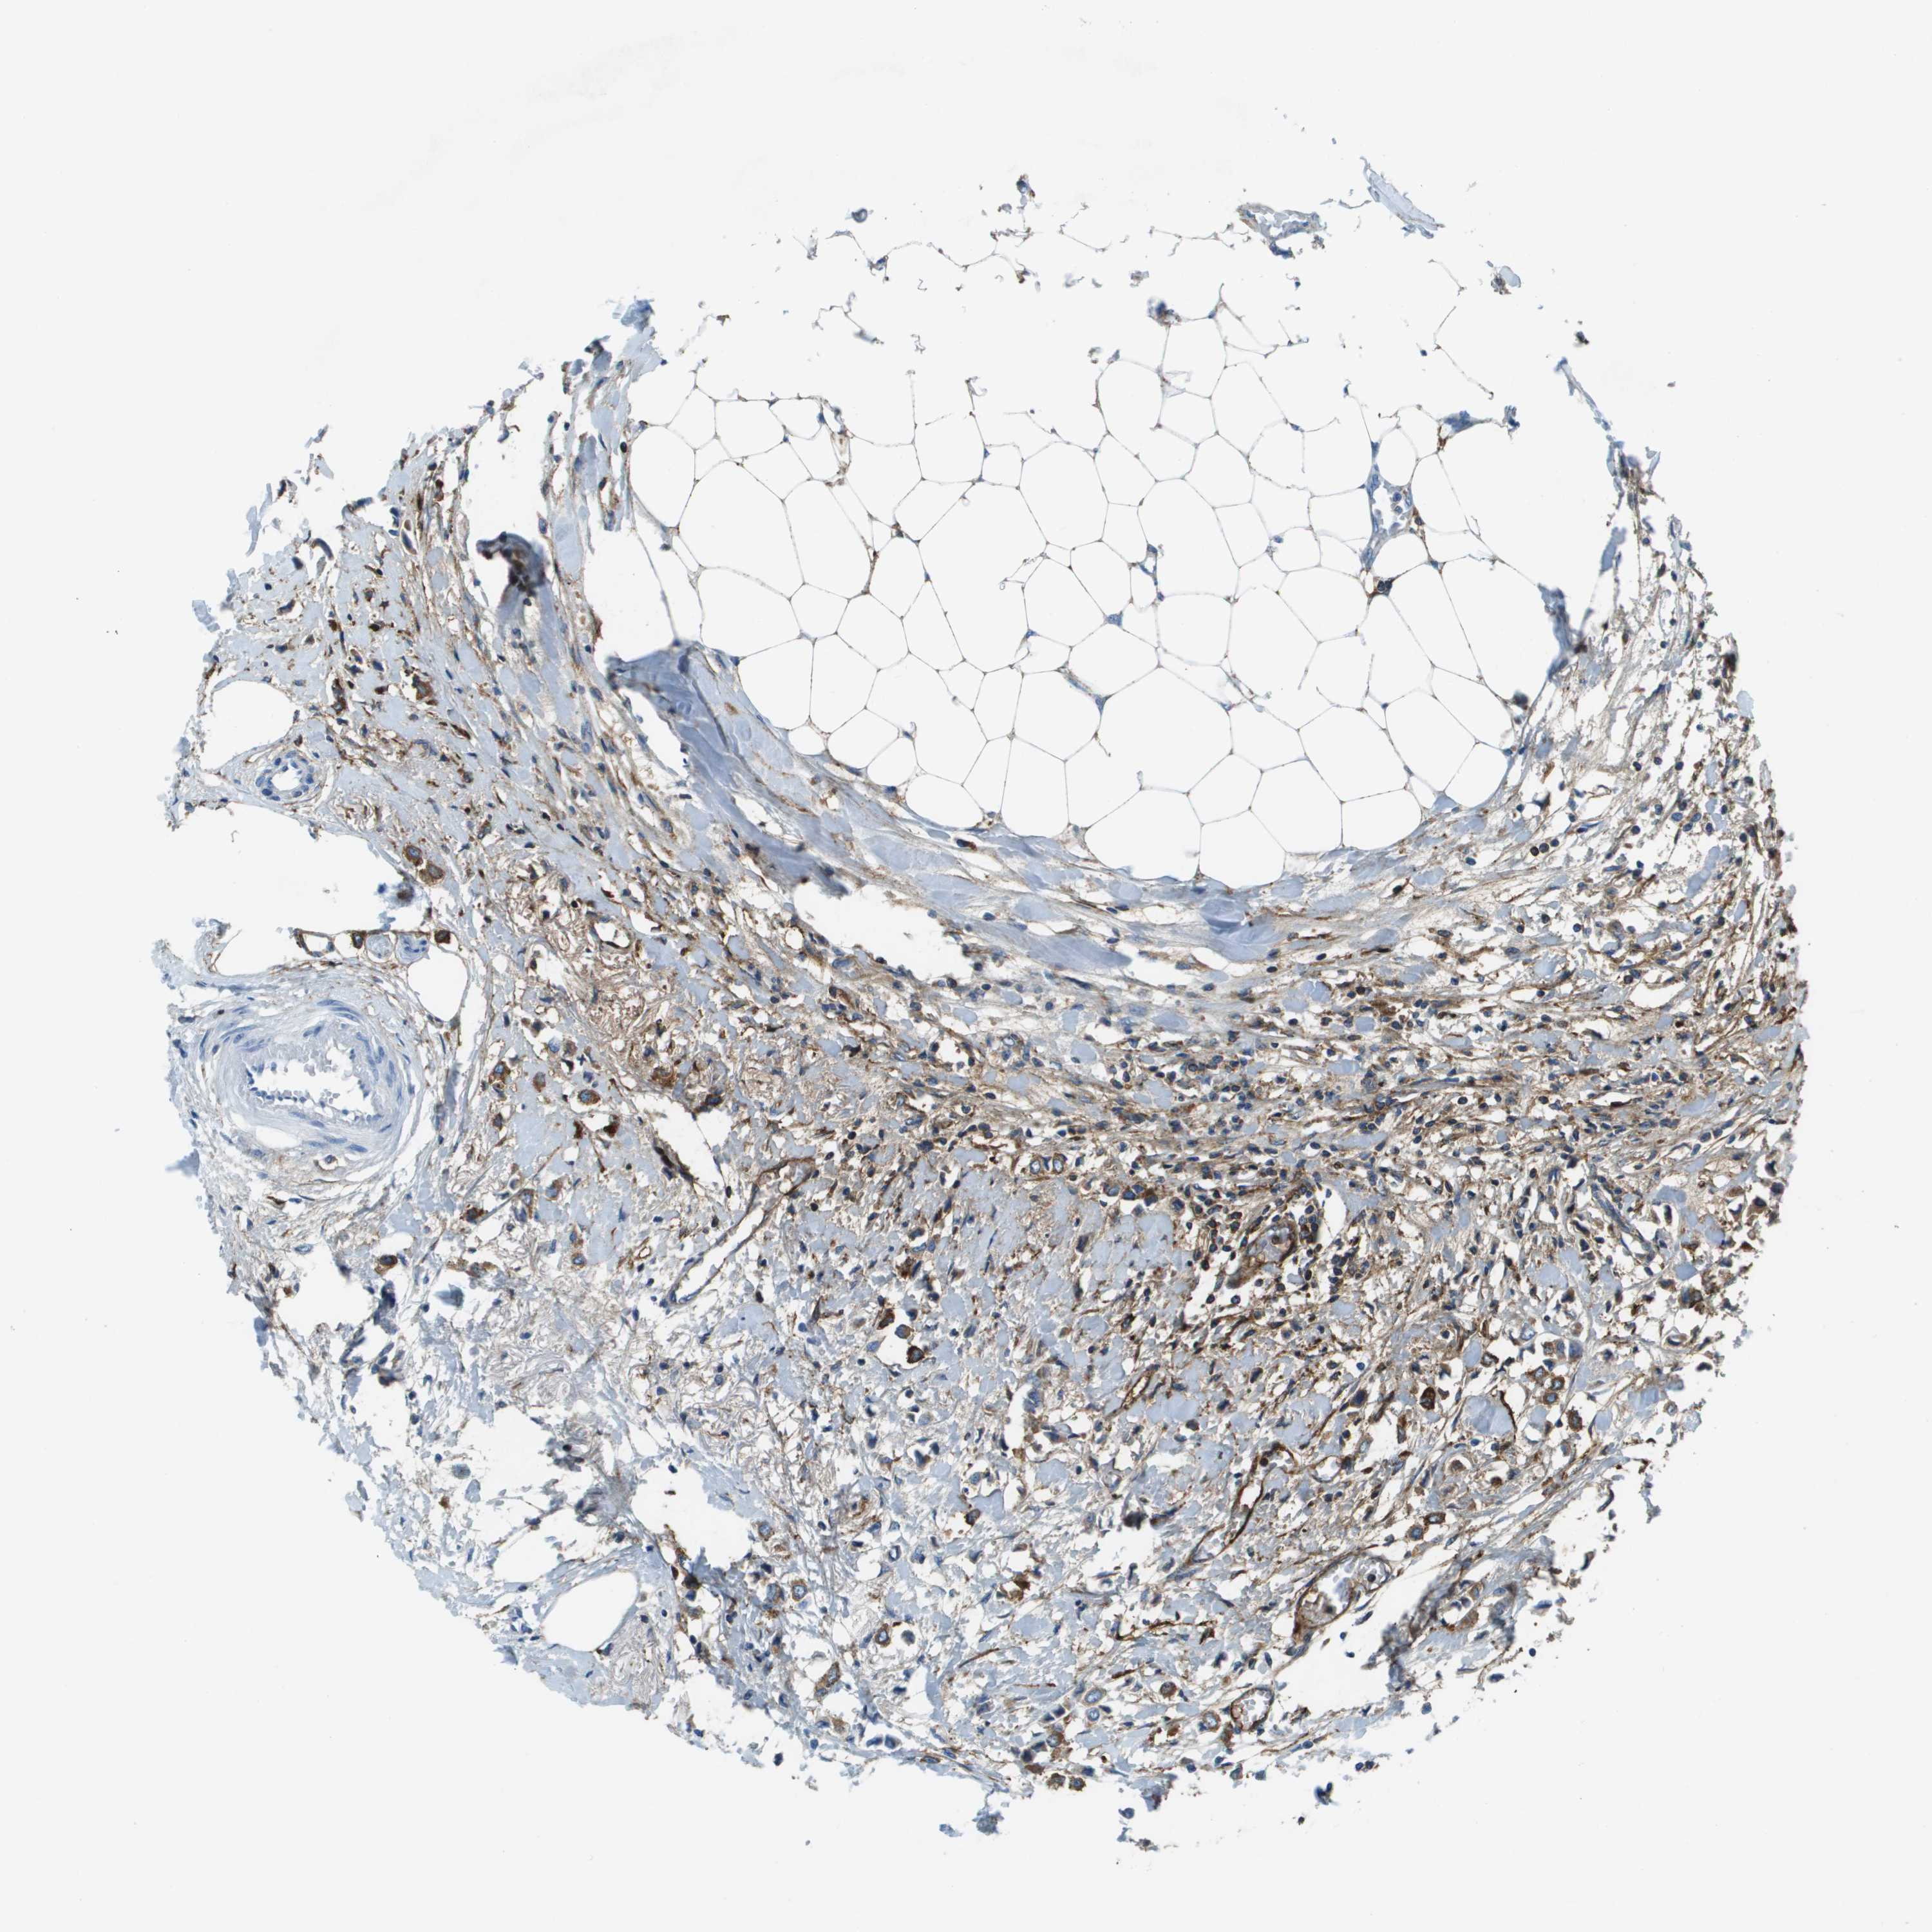

BRCA TCGA BRCA VALIDATION PROTEIN EXPRESSION

ANTIBODIES

AND

VALIDATION